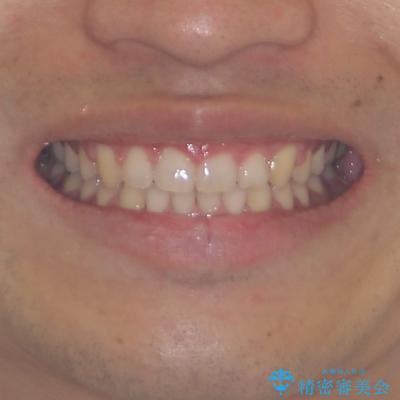

深い咬み合わせと隙間の空いた歯列をワイヤー矯正で改善

- 前歯の隙間と深い咬み合わせを改善したいとのことで来院された患者様です。

マウスピース矯正の自己管理が面倒とのことで、ワイヤー矯正により治療を行うこととしました。

奥歯の咬み合わせは理想的な状態であったため、ワイヤー矯正でもインビザラインでも比較的容易に対応可能でした。